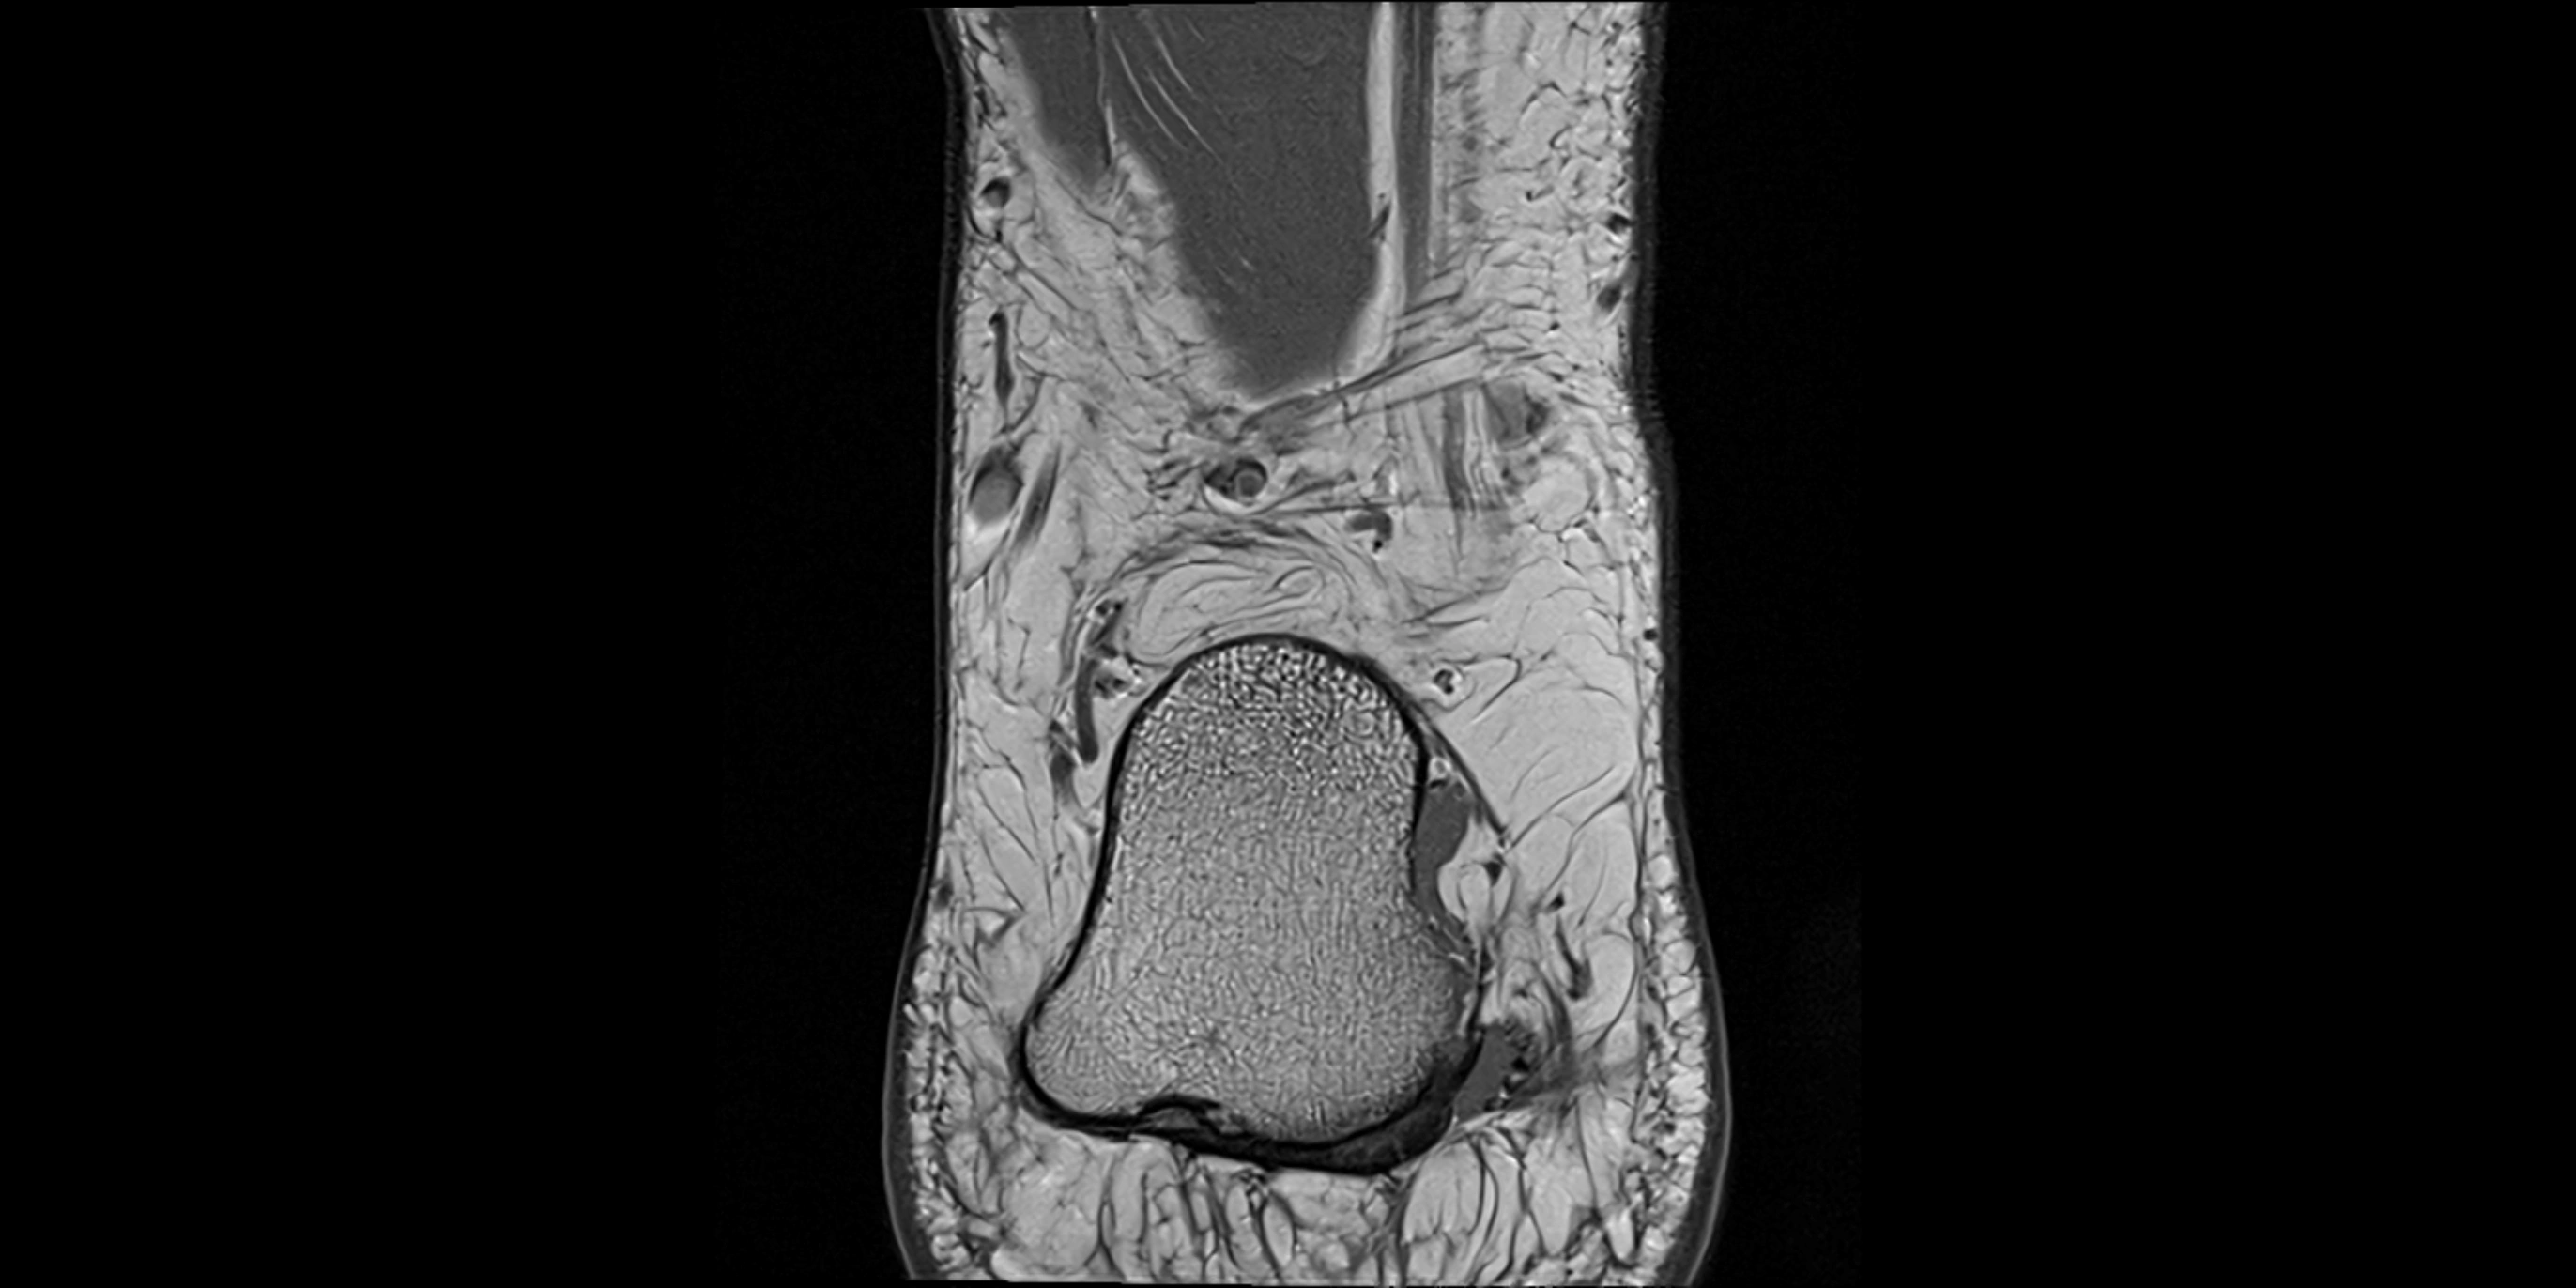

MRI image

image